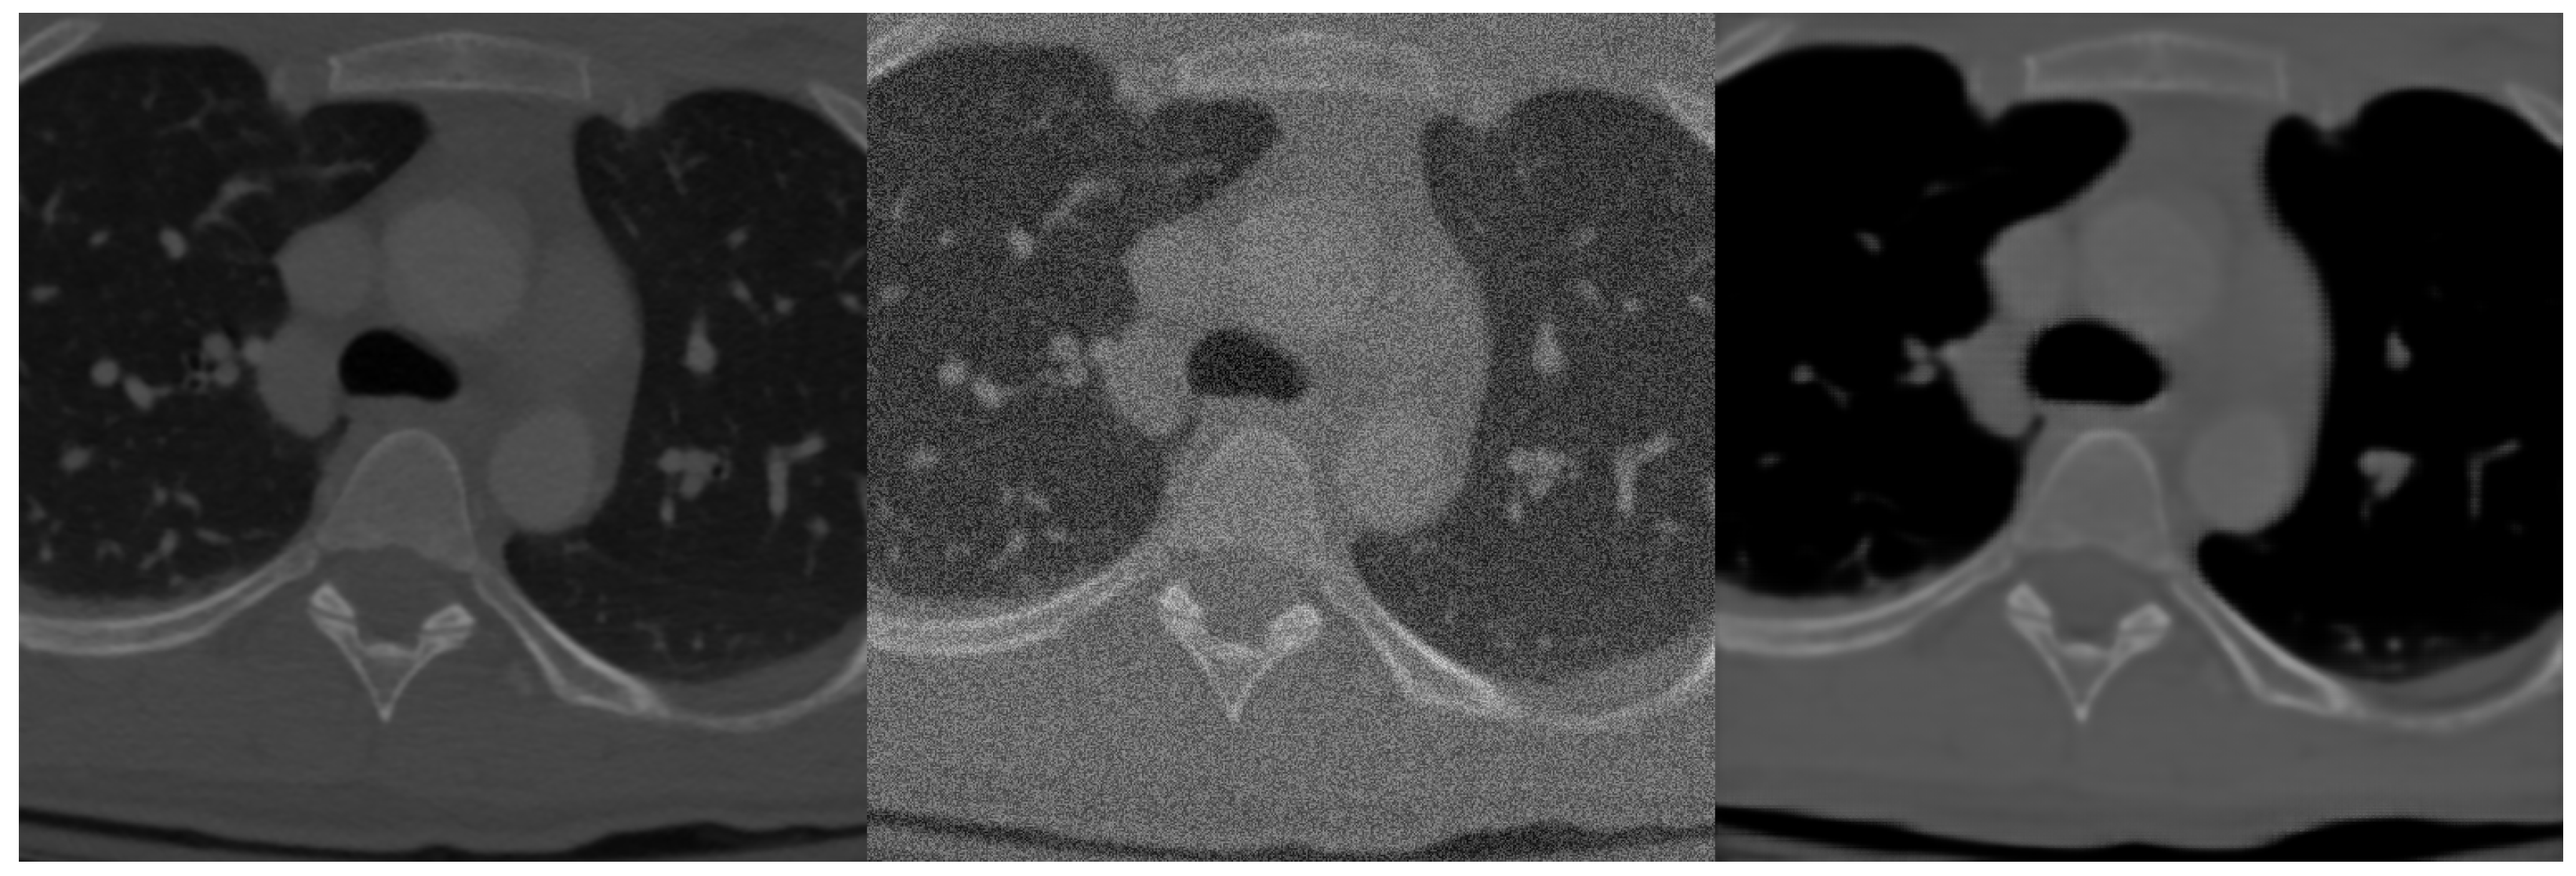

2.1.4. Denoising Data Preparation

After initial segmentation experiments with the spine dataset we found it is a much more challenging task than the brain volumetric segmentation and training the network only on the dataset was not sufficient for highly precise segmentation. Instead of data augmentation, which for 3D algorithms greatly expands computation time, we used denoising autoencoder pre-training. Principle with this method lies in the fact that we add noise to the training data and let the neural network to learn the representation between noised and denoised data and therefore extracting features of the input image and proper learning of deep layers. An example of original training image, image with added noise and denoised image by our network can be seen in Figure 4.

Figure 4.

Example of data before adding linear noise (left), with added linear noise (middle) and after denoising by neural network (right).

Training dataset consisted of normal training data with added linear 30 percent noise with normal distribution. The network was trained to denoise data into its original form. As seen in Figure 4 the network learned the representation properly, denoised image only lacks higher level of details [20].